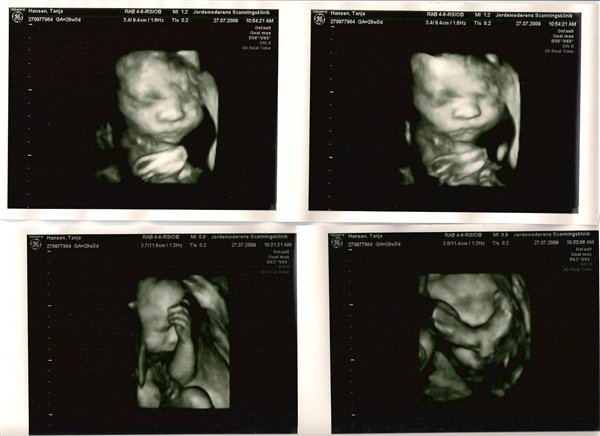

Jeg har lige været til en 3D/4D scanning (27+0), hvilket var en kæmpe oplevelse. Jeg venter en dreng på foreløbig 976 gram

Denne tråd er for alle os som har fået foretaget sådan en scanning. Jeg tænkte det kunne være sjovt at smide nogle fotos op af vores bebzere, da de lå i maven. I profil og forfra.

Skriv gerne hvilken uge scanningen er foretaget, samt evt. hvad køn det er